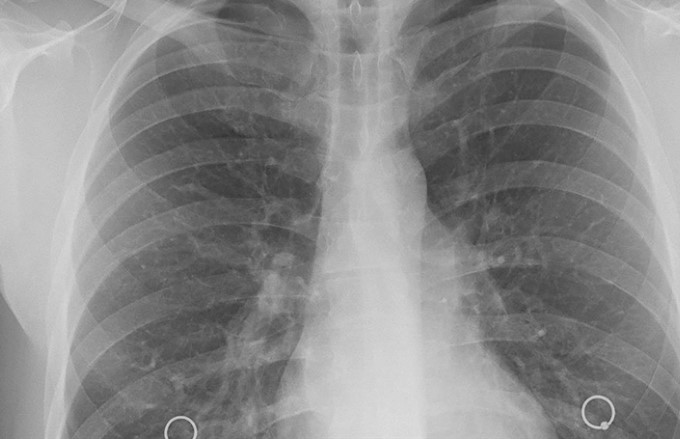

İyi huylu akciğer kanseri belirtileri nelerdir diye bakıldığında bu türün lezyonları genellikle belirtisizdir ve tesadüfen görüntüleme testlerinde rastlanmaktadır. Ancak büyüklüğü arttıkça ya da belirli noktaya ulaştığında bazı belirtiler kendini gösterebilmektedir. İyi huylu akciğer kanseri belirtileri nelerdir diye bakıldığında ise: